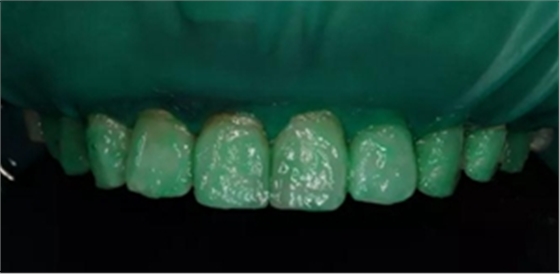

2,使用紅標45μm微米和黃標25μm粒度車針仔細緩慢打磨去除釉質表面高氟鈣化的斑塊和釉質凹坑0.05-0.1mm后,車針打磨后要再使用低速慢機用矽粒子拋光去除釉質表面浮釉(松風矽粒子、樹脂拋光輪),下圖是微打磨后。

(下圖是上頜打磨后與下頜術前未研磨對比,區(qū)分打磨效果和目的)

3,icon鹽酸處理兩分鐘,暴露釉質表面孔隙,表面礦化層厚度減少更明顯,更適合做滲透前釉質處理,獲得更好的滲透深度。(一定要使用橡皮障)